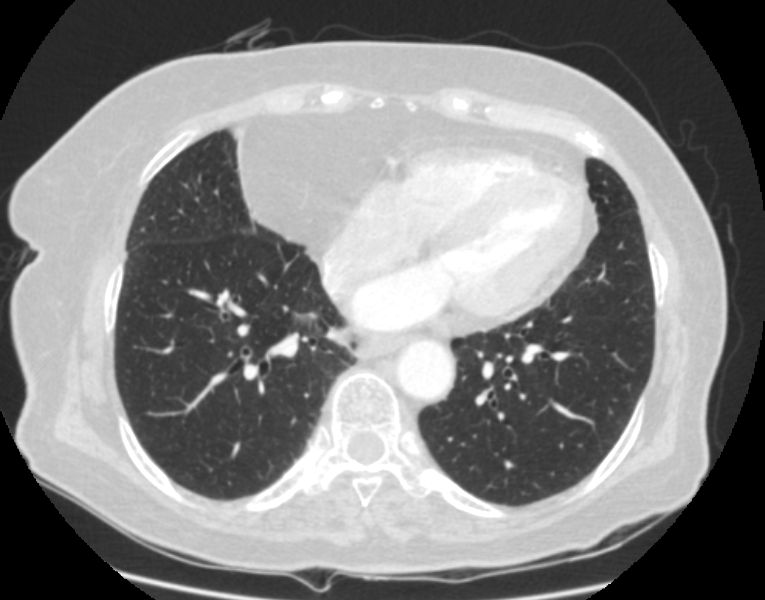

F/73

DM, HTN °ú°Å·Â ÀÖ´Â ºÐÀ¸·Î hip osteoarthritis ·Î THR ½ÃÇà ¿¹Á¤ÇÏ´ø Áß preop CXR abnormality ·Î ÀÇ·ÚµÊ.

never smoker, Á÷¾÷ : ¹«

Cough/Sputum (-/-)

Dyspnea/DOE (-/-)

CBS s rale

wheezing (-)

< Chest CT >